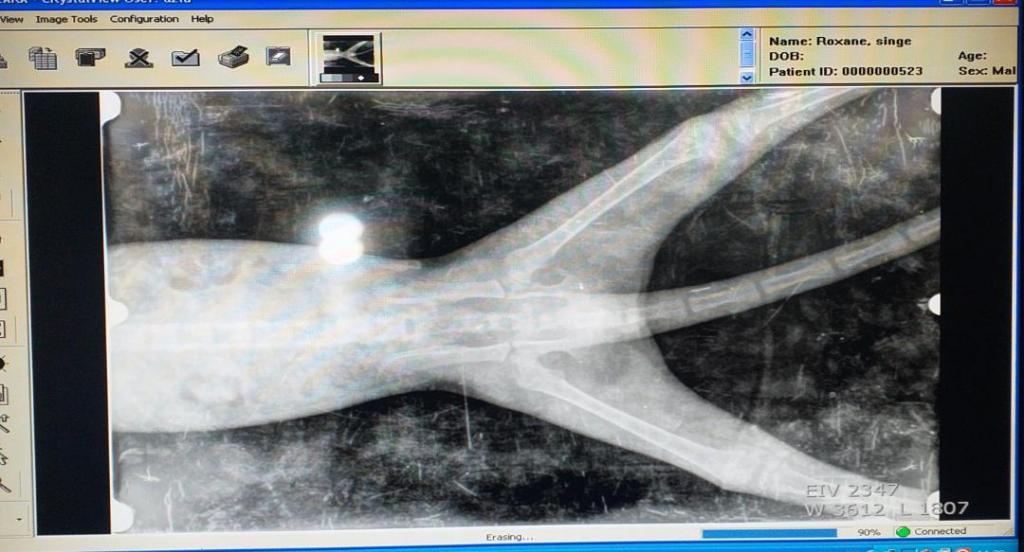

En effet, à son arrivée, nous avons constaté un problème de motricité (il ne marchait pas et pleurait de douleurs) et avons fait de suite des radios de son bassin.

Le constat n’était pas réjouissant: les hanches étaient fracturées à deux endroits et il lui fallait du Calcium mais aussi du repos, une cage basse et petite pour éviter les mouvements et pour faciliter la calcification.

Cependant, un mois après son arrivée, nous venons de refaire une radio et il y a tout de même une progression puisqu’un côté commence à se resouder.